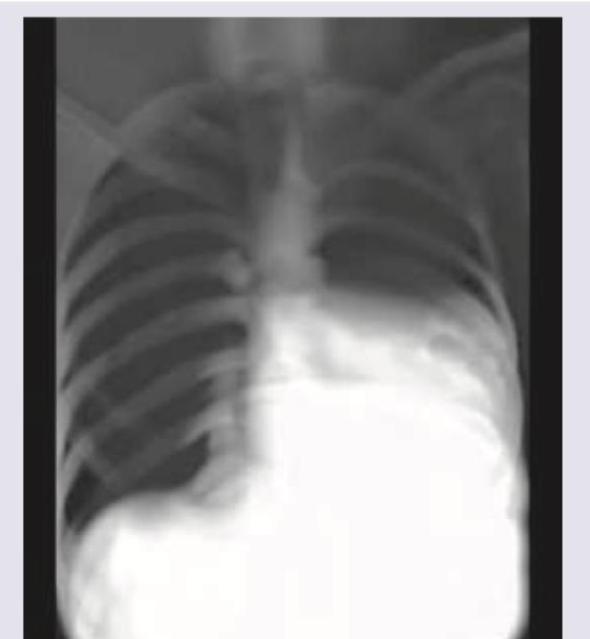

Explanation: ***Pneumothorax*** - A **pneumothorax** is characterized by the presence of **air in the pleural space**, which typically appears as a **lucent area** without lung markings and a displaced visceral pleural line on X-ray. - The presented chest X-ray shows **dense opacities at the lung bases**, consistent with fluid accumulation (**pleural effusion**), not air. *Left-sided pleural effusion* - The image clearly shows significant **opacification of the left hemithorax** with blunting of the **costophrenic angle** and obscuring of the left hemidiaphragm. - This finding is consistent with a large amount of fluid, indicating a **left-sided pleural effusion**. *Mediastinum shifted to right* - The **trachea** and **cardiac silhouette** are visibly displaced towards the **right side** of the chest. - This shift is a consequence of the large **left-sided pleural effusion exerting mass effect** and pushing the mediastinal structures away from the affected side. *Bilateral ICD tubes* - There are discernable radiopaque lines extending into both pleural spaces, representing **bilateral intercostal drainage (ICD) tubes**. - These tubes are placed to drain the **accumulated pleural fluid** from both the right and left sides.